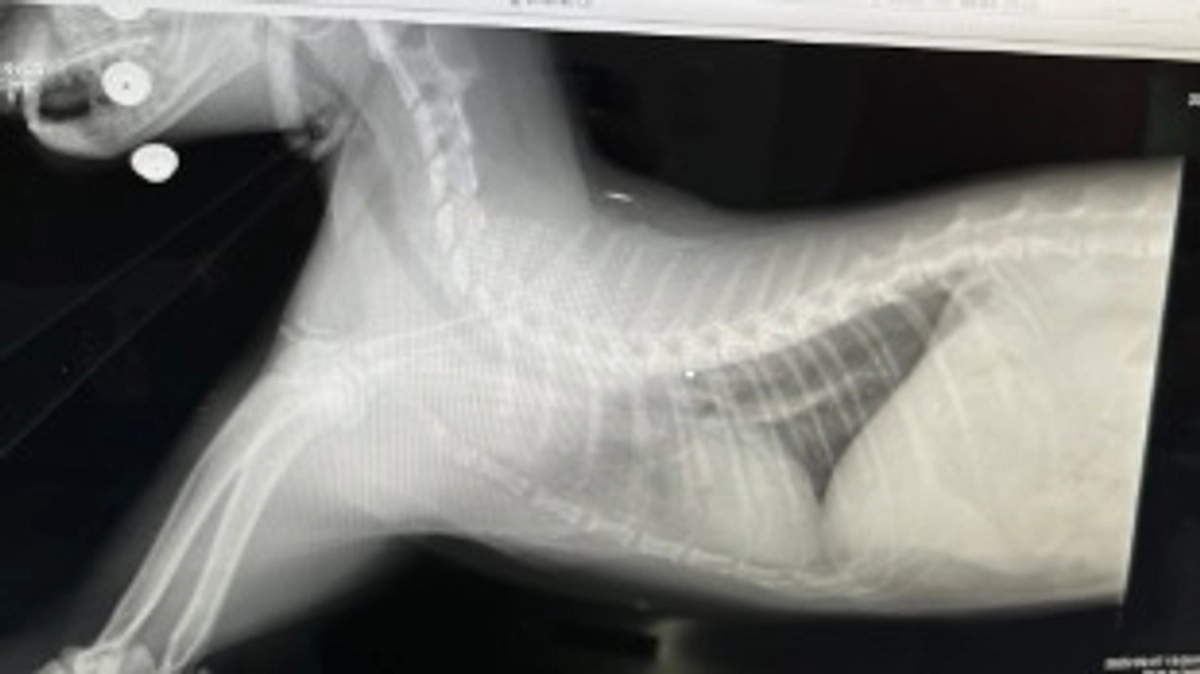

レントゲンを撮ってもらい、肺と心臓部のエコー検査もしてもらいましたが、

やはり前回と同じように心臓付近にくもりが写りました。